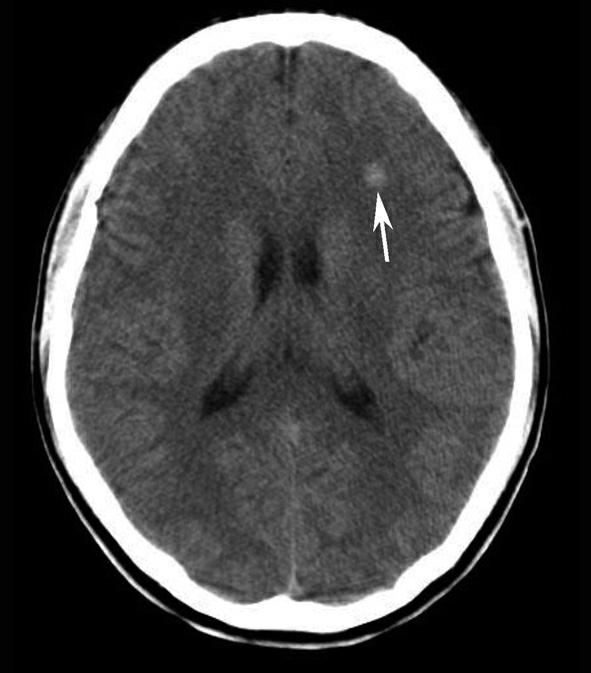

松果体、苍白球在成人期常出现钙化,属生理性钙化,一般无病理意义。需注意勿误诊为出血灶,尤其是单侧苍白球钙化时(图1-2-28)。

图1-2-28 苍白球生理性钙化

A.双侧苍白球对称性钙化,呈高密度影(箭);B.左侧苍白球钙化(箭),右侧苍白球钙化不明显